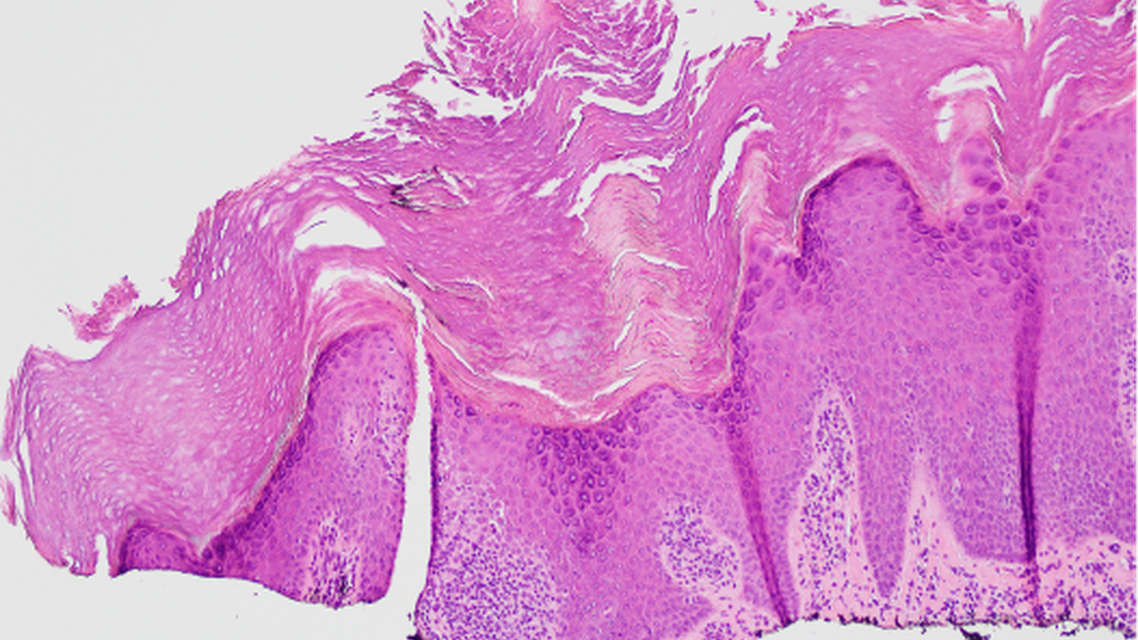

At follow-up, the lesions showed no improvement with the prescribed treatment, so a shave biopsy was performed. Histopathological analysis demonstrated verrucous epidermal hyperplasia with focal granular layer loss and suprapapillary thinning as well as nonspecific chronic dermal inflammation, consistent with a diagnosis of verrucous psoriasis (Figure 3). HPV in situ hybridization testing was negative, confirming the diagnosis of VP.

Figure 3. Hematoxylin-eosin stain; original magnification, ×10. Verrucous epidermal hyperplasia with focal granular layer loss and suprapapillary thinning consistent with verrucous psoriasis. (Department of Pathology, Louisiana State University, New Orleans, LA)